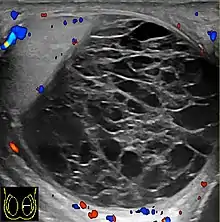

Transscrotal ultrasound

Sonography of a normal testis. The normal testis presents as a structure having homogeneous, medium level, granular echotexture. The mediastinum testis appears as the hyperechoic region located at the periphery of the testis as seen in this figure.